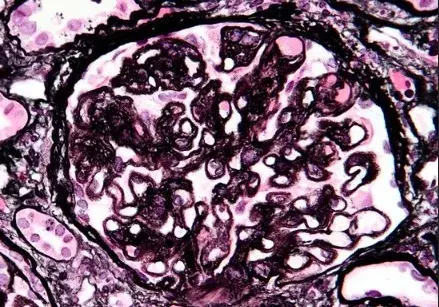

Nefropatia Membranosa: e se o paciente não responder ao tratamento inicial?

Como fazer o tratamento da Nefropatia Membranosa de forma prática!